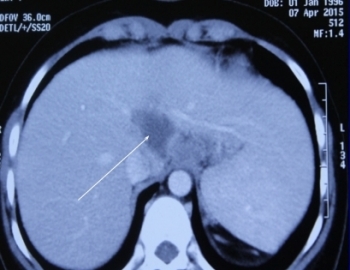

Chữa khỏi bệnh lao gan hiếm gặp trên thế giới cho nữ sinh

Theo các chuyên gia y tế, lao gan là bệnh hiếm gặp, y văn thế giới mới ghi nhận 2 ca. Ca bệnh đầu tiên ở nước ta vừa được các bác sĩ Bệnh viện Chợ Rẫy (TP HCM) chữa khỏi.